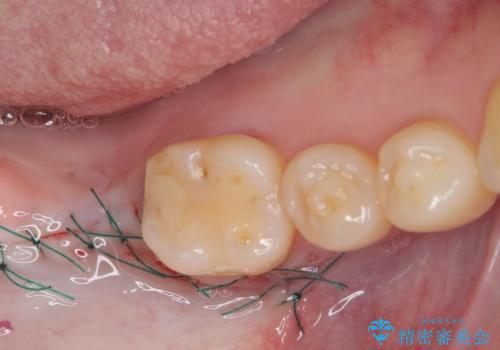

ストローマン社のSLActiveというインプラントを使用し、インプラント埋入からクラウンが装着されるまで3ヶ月弱という短期間で終えることができました。

咬み心地はもちろん、清掃性もご自分の歯とほとんど変わらない状態となり、患者様には大変満足していただきました。